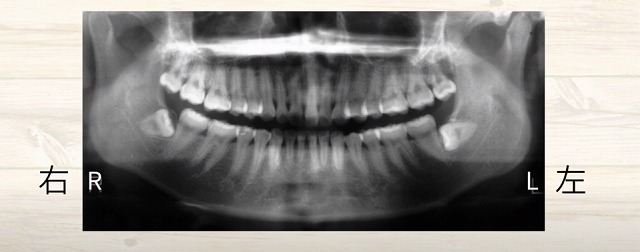

レントゲンの見方

真ん中からだいたい対称的で左右が

Rが右です左がLです。

そしてレントゲンの見方で知っておいてほしいことは、

硬いものが白く写るということです。

お口の中で

硬いものとは何か?

歯の頭

歯の根っこ

そして

歯の根っこを支えている骨

が硬いです。

歯茎や神経や血管は硬くありません。

ですので、

レントゲン写真には写ってこないですね